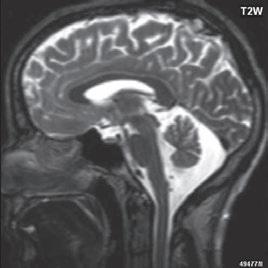

I.1.7 Chiariho malformace (ArnoldovaChiariho malformace)

Rozlišujeme tři formy (typy) této malformace. Chiari I je charakterizován sestoupením mozečkových tonzil do foramen okcipitale magnum do oblasti krční páteře (u dospělých jsou tonzily mozečku max. 5 mm pod úrovní baze lební, u malých dětí (do 10 roků) do 6 mm. Tonzily bývají na podélném řezu přirovnávány ke klínům, které jako by byly zatlučeny do týlního otvoru „pek like“. Chiari II malformace je ve 100 % doprovázena otevřeným spinálním dysrafismem (obvykle myelomeningokélou). Chiari III lze definovat jako Chiari II + okcipitální nebo cervikální encefalomeningokéla. Chiari IV, kde je navíc přítomna hypoplazie mozečku, do této skupiny nezařazujeme, vývojově patří do poruch ventrální indukce.

Zobrazení

Chiari I: CT a MR zobrazí malou zadní jámu lební, absenci cisteren zadní jámy lební, pokles tonzil, krátký a konkávní klivus, poruchu cirkulace mozkomíšního moku v oblasti foramen magnum a následný hydrocefalus. MR navíc může prokázat edém krční míchy a ve vysokém procentu případů hydrosyringomyelii.

Chiari II: CT a MR zobrazí malou zadní jámu lební, absenci nebo výraznou redukci cisterny cerebelomedulární a dalších kmenových cisteren, konkávní klivus. Mohou být abnormality v oblasti foramen okcipitale magnum, nízký úpon tentoria, někdy absence nebo fenestrace falx cerebri. MR lépe ukáže kaudálně uloženou a protáhlou IV. komoru (někdy je přirovnávána až ke stéblu slámy), protažený pons a další možné, přidružené abnormality (hydrosyringomyelii, agenezi, hypogenezi nebo fenestraci corpus callosum…).

Obr. I.1.7a Sestup mozečkových tonzil (šipka), Chiariho malformace I

Obr. I.1.7b Sestup mozečkových tonzil, „pek like“ (šipka), Chiariho malformace I c d